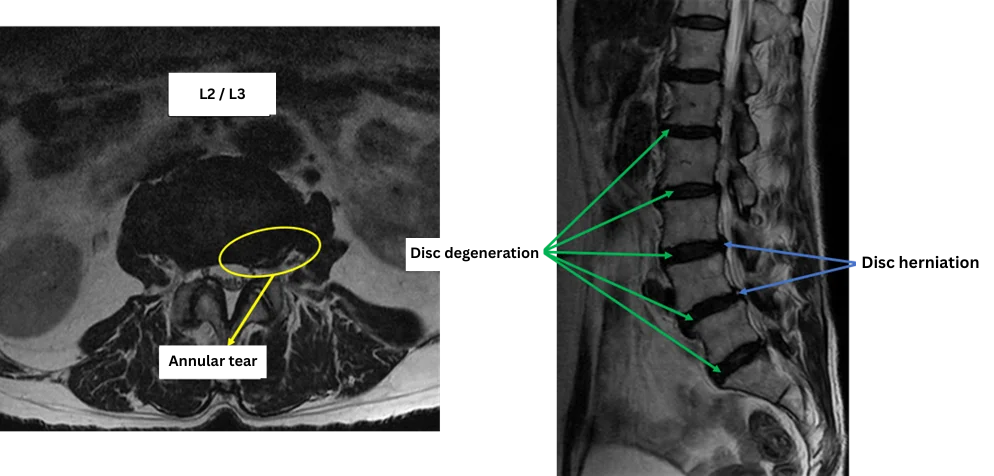

Imaging and findings

L1/2: Disc degeneration

L2/3: Disc degeneration, annular tear

L3/4: Disc degeneration, disc herniation

L4/5: Disc degeneration, disc herniation, annular tear

L5/S: Disc degeneration

The above findings were also observed on the imaging.

Disc degeneration, disc herniation, and annular tears were observed at L2/3, L3/4, and L4/5, which are considered the most likely causes of the primary symptoms.